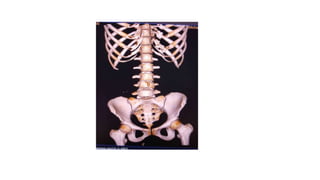

ANATOMY OF PELVIS

• The bony pelvis consists of innominate bones, each

with three parts (ilium, ischium and pubis), sacrum

and coccyx.

• It protects the pelvic viscera, provides attachment

for the muscles of the trunk and lower limb, and

enables stable transfer of the body weight from the

spine to the femur.

• Its divided into false (major) and true (minior)

pelvis, by the ileopectineal line: the smaller inferior

part is the true pelvis and the larger superior part is

the false pelvis.

• The false pelvis is formed mainly by the iliac fossae and

is largely filled by the iliopsoas muscles.

• The true pelvis is bounded posteriorly by the sacrum

and coccyx, laterally by the obturator membranes,

sacrospinous ligaments, and anteriorly by the pubic

bones.